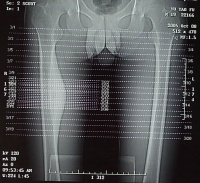

大腿

的X光片